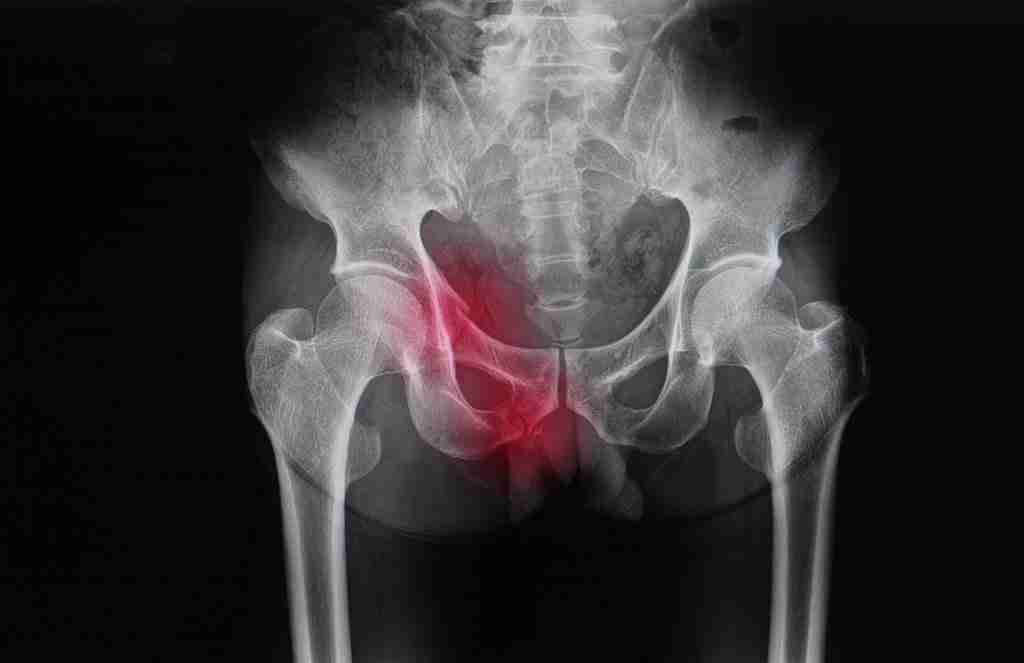

损伤性骨折

不足性骨折是指没有已知机制或已知创伤的小骨折或应力性骨折。

这些骨折是由于负重状态和活动量的改变导致新植入的骨质承受不了而发生的。

患者可能会在毫无征兆的情况下开始感到髋部、大腿甚至骨盆疼痛。

不幸的是,这些骨折可能发生在置换部位以外的部位,如耻骨横突或骨盆的其他部位,这是因为新置换的髋关节所承受的压力和负荷发生了变化。

通过影像学检查,可以发现这些骨折并进行适当治疗。

如果骨折不能自行愈合,可能需要休息或进行手术固定。